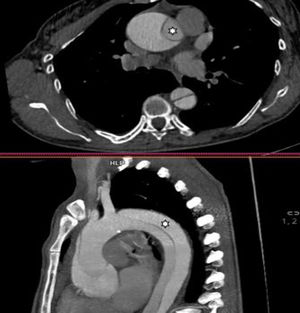

Mujer de 47 años con antecedente de aortopatía bicúspide en abuelo paterno; los padres fallecieron jóvenes en un accidente de tráfico. Por palpitaciones, se solicitó un ecocardiograma ambulatorio, observando un ventrículo dilatado con un diámetro telediastólico del ventrículo izquierdo de 71mm, indexado 3,4mm/m2, fracción de eyección del ventrículo izquierdo del 55-60% además de una válvula aórtica bicúspide con fusión entre los velos coronarianos derecho e izquierdo que condicionaba una insuficiencia aórtica severa (fig. 2) con una raíz aórtica de 40mm. Se solicitó una tomografía computarizada para estudio prequirúrgico (fig. 1) que se realizó tres semanas después, evidenciando una disección aórtica tipoA de Stanford/DeBakeyI con un flap intimal a nivel de la raíz que se extendía longitudinalmente (fig. 3) y de forma espiroidea hasta la arteria ilíaca común izquierda, involucrando el tronco braquiocefálico derecho sin comprometer su flujo. Ante estos hallazgos se trasladó a la unidad de cuidados intensivos cardiológicos para intervención quirúrgica urgente, realizándose cirugía de David con reimplante independiente del tronco braquiocefálico.